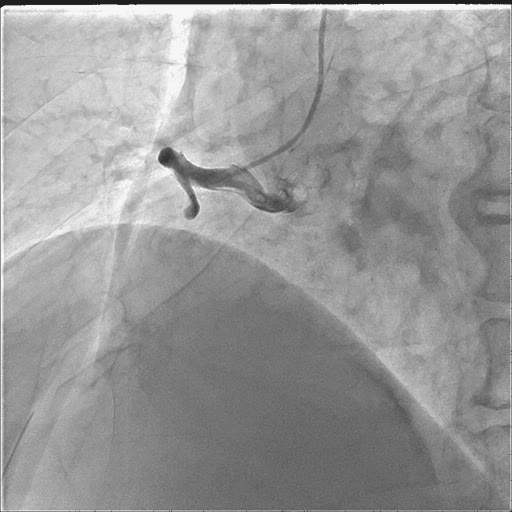

抓紧时间完成造影:

造影完即刻在透视下心尖部进针置管,抽出“不凝血”200ml。患者意识好转,一般情况好转,生命体征改善,血压回升至125/75mmhg,心率也下来一些,心电监护显示:窦性心律 88次/分。

暂时缓解了心脏压塞,但迂曲的血管,是下一个难关!导丝、球囊根本不能到位,在延伸导管的帮助下完成球囊扩张及支架植入。

支架植入也是非常困难,最后经过深插GC,延伸导管尽量靠前支撑下,完成了支架植入。开通后可以发现RCA非常大,范围很广。